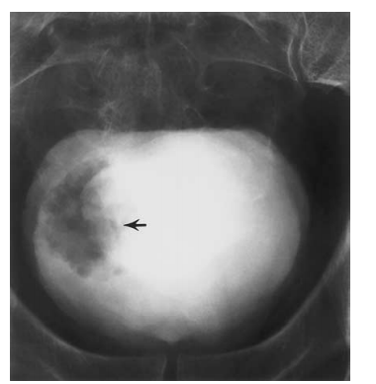

multifocal TCC